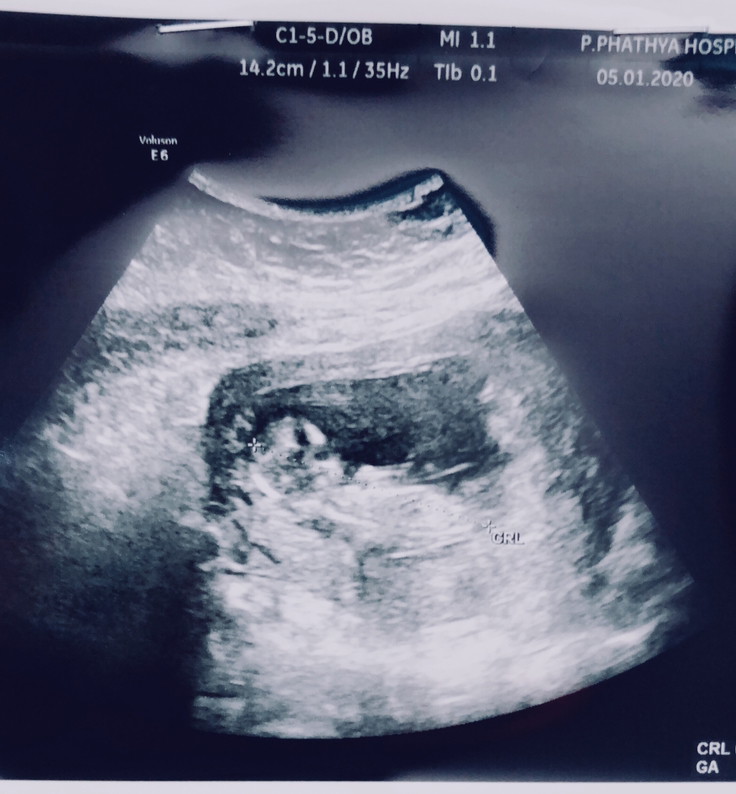

12 week ka

12 วีค4วันจ้า

12วีคค่ะ💕

ตอน12wค่ะ

12วีคค่ะ

12w2d จ้า